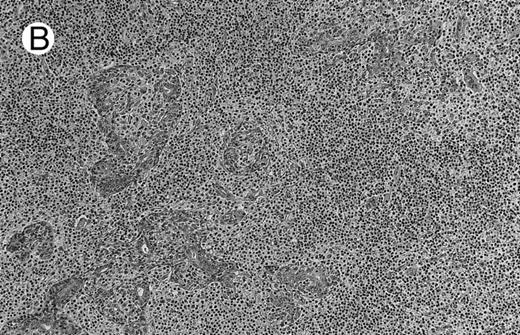

Low-grade marginal zone B-cell lymphoma (MZL; REAL classification)9 comprised the largest number of cases (n = 12). Nine of them were low-grade MALT type lymphomas involving parotid, stomach, bronchus, buccal mucosa, and skin. The histological pattern was relatively homogeneous, showing diffuse lymphoid infiltrates that included small lymphocytes with round nuclei or with plasma-cell differentiation and/or centrocyte-like cells with indented nuclei (Fig 1A). Lymphoepithelial lesions were observed in each case, regardless of the tissue involved (Fig 1B). Monocytoid cells characterized by a larger cytoplasm and a slightly irregular nucleus were mixed with centrocyte-like cells in 2 cases of MALT lymphoma arising in the parotid (cases no. 3 and 15). There were also scattered occasional large cells (centroblast or immunoblast). In cases no. 3, 6, and 15, remnants of germinal centers with partial follicular colonization were observed (Fig 1C). Beside these 9 low-grade-type mucosal lymphomas, 3 nodal lymphomas (cases no. 8, 10, and 14) had histological features similar to that of low-grade MALT type lymphoma because they showed a typical lymphoplasmacytoid infiltration with a variable proportion of blasts. In 2 cases, the presence of numerous immunoblasts or centroblasts, mixed with small lymphoplasmacytoid cells or plasma cells, indicated an evolution to a more aggressive lymphoma (Fig 1D). The third nodal lymphoma showed a small lymphocytic or lymphoplasmacytoid diffuse infiltrate associated with intrasinusal large nests of monocytoid cells. This histological picture is characteristic of monocytoid B-cell lymphoma (MBLC; Fig 1E).

NHL associated with SS (hematoxylin-eosin stains). (A) Case no. 13. Low-grade B-cell lymphoma of MALT type in the stomach, composed mainly of centrocyte-like cells with a few small lymphocytes and plasma cells. (B) Case no. 15. Low-grade B-cell lymphoma of MALT type in the parotid. Lymphoepithelial lesions are numerous, surrounded by centrocyte-like cells. (C) Case no. 6. Remnants of a germinal center in a low-grade B-cell lymphoma of MALT type in the parotid.